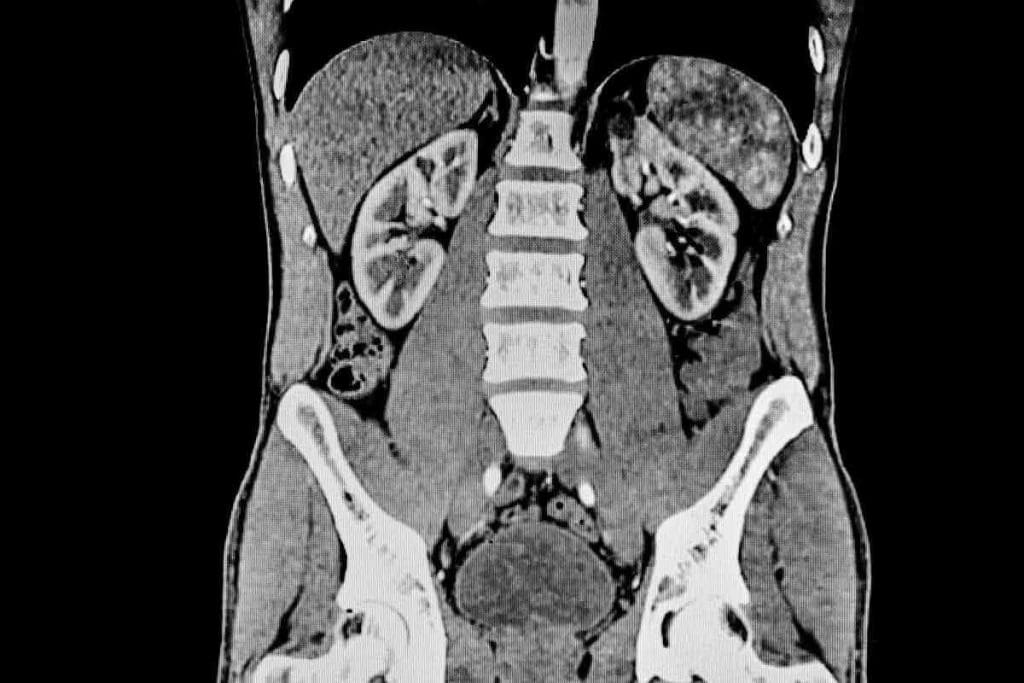

Characteristics of a Healthy Liver on CT

A healthy liver on a CT scan looks uniform and has clear edges. It’s important to compare it to a normal liver scan to spot liver diseases.

Normal Appearance and Density

A normal liver looks the same all over on CT scans. It’s a bit denser than the spleen. Its density is even, with a value slightly higher than the spleen’s.

Enhancement Patterns in Normal Tissue

On a contrast-enhanced CT scan, the liver shows a special pattern. It enhances in a multi-phasic pattern. This pattern helps doctors see how well the liver is working and if there are any problems.